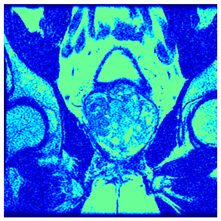

| Image | nt = 3 | nt = 4 | nt = 5 | nt = 8 |

|---|---|---|---|---|

| 1 | ![]() | ![]() | ![]() | ![]() |

| 2 | ![]() | ![]() | ![]() | ![]() |

| 3 | ![]() | ![]() | ![]() | ![]() |

| 4 | ![]() | ![]() | ![]() | ![]() |

| 5 | ![]() | ![]() | ![]() | ![]() |

| 6 | ![]() | ![]() | ![]() | ![]() |

| 7 | ![]() | ![]() | ![]() | ![]() |

| 8 | ![]() | ![]() | ![]() | ![]() |

| 9 | ![]() | ![]() | ![]() | ![]() |

| 10 | ![]() | ![]() | ![]() | ![]() |

| 11 | ![]() | ![]() | ![]() | ![]() |